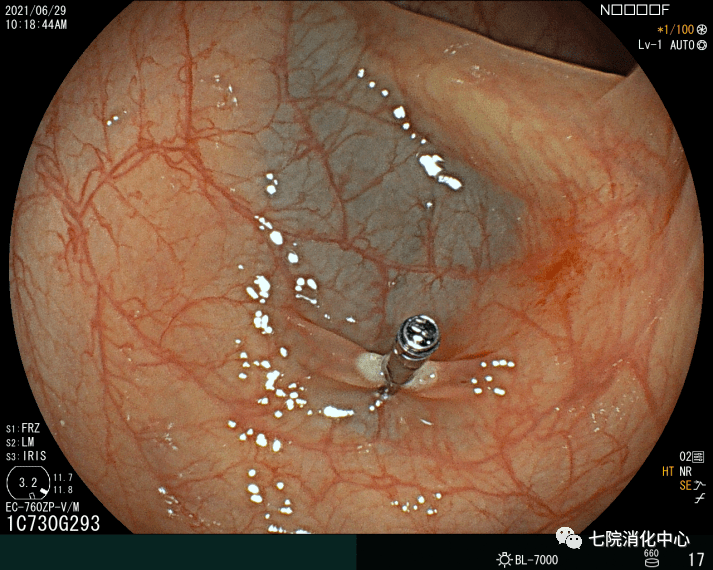

4、ESD:

ESD相对于EMR而言 , 可最大限度地减少肿物的残留和复发 。 ESD通常应用>20mm、非颗粒样侧向发育病变 。 ESD相对于传统的分片黏膜切除术来说是一种复发率低、可获得更好的病理标本的技术 。 ESD的不足是穿孔率高、过程耗时 。 多项研究表明 , ESD穿孔率约5% 。 大量研究报告了ESD的临床结果 , 整块切除的疗效好以及大型浅表结直肠肿瘤的长期低复发率 。